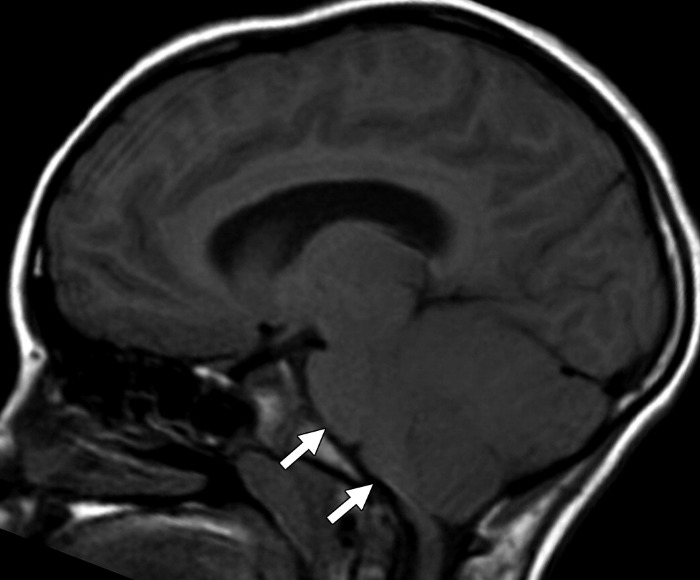

Корональная Т2ВИ-томограмма показывает гиперинтенсивные области инфарктов в области полосатого ядра слева.

На сагиттальной FLAIR томограмме мозжечок выглядит диффузно увеличенным, оттесняя кпереди структуры ствола.